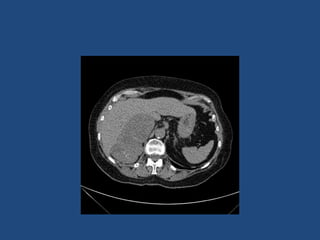

Adrenal imaging

Imaging

•

>6cm high suspicion of malignancy

3-6cm repeat imaging in 3-6M

Delayed washout on contrast is suggestive

most are often inhomogeneous, irregular

margins

• Look for invasion of IVC

• Always do CAP and consider bone scan and

pet if in doubt

• Don’t ever biopsy (tumour spill)

Imaging • • • • >6cm high suspicionof malignancy 3-6cm repeat imaging in 3-6M Delayed washout on contrast is suggestive most are often inhomogeneous, irregular margins • Look for invasion of IVC • Always do CAP and consider bone scan and pet if in doubt • Don’t ever biopsy (tumour spill)